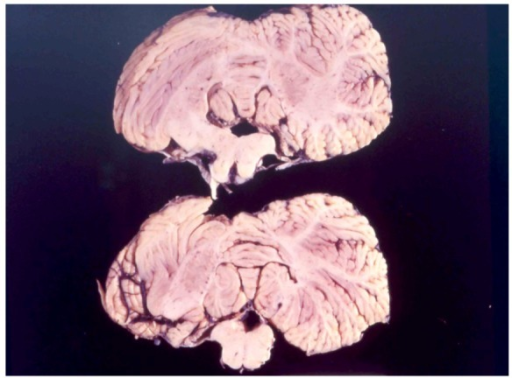

3. 2. 신경병리학적 특징

쿠루병에 감염된 개인에 대한 연구는 이 질병이 뇌에 미치는 영향을 구체적으로 밝혀냈다. 초기 단계의 감염된 개인은 무력감, 협응력 저하, 떨림, 발가락과 발의 굽음 현상을 경험할 수 있다.[15] 이러한 균형 및 조정의 어려움은 뇌 신경 세포의 손상과 관련이 있다. 클라초(Klatzo) 등의 연구에 따르면, 쿠루병에 감염된 뇌의 뉴런(신경 세포)은 건강한 뉴런에 비해 비정상적으로 작고 색이 옅으며, 특징적인 변형으로 인해 마치 "좀먹은" 것처럼 보인다.[15] 이러한 신경 세포의 이상 소견은 크로이츠펠트-야코브병(CJD) 환자의 뇌에서도 유사하게 관찰된다.[15] 프리온 단백질로 인한 이러한 뇌 손상은 점진적인 신경 기능 상실로 이어진다.쿠루병의 잠복기는 보통 5년에서 20년 사이이며, 일단 증상이 발현되면 평균 12개월의 임상 경과를 거쳐 사망에 이른다. 증상은 크게 생리적 증상과 신경학적 증상으로 나뉘며, 진행 단계에 따라 특징적인 양상을 보인다. 체간의 운동실조가 대표적이며, 이에 선행하여 두통, 관절통, 다리의 떨림이 나타날 수 있다. 떨림은 대부분의 감염자에게서 관찰된다.